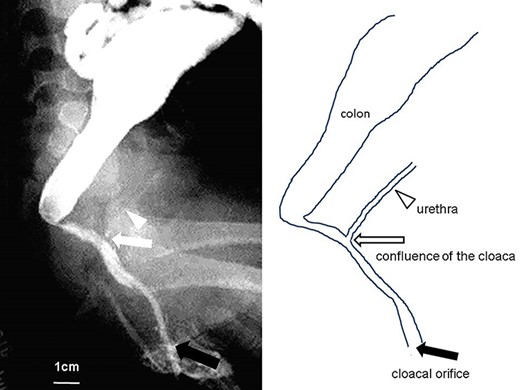

Fistulography and schema of the cloaca, 7 months of age. The common channel is >3 cm in length, and the vagina is defective (black arrow, cloacal orifice; white arrow, confluence of the cloaca; white arrowhead, urethra).

A female infant was born at 38-week gestational age, weighing 2570 g. After birth, she was diagnosed with a cloacal malformation (Fig. 1a). At 1 day of life, the patient underwent double-barrel colostomy and fistulography of the cloaca (Fig. 1b); the results of the latter were suspicious for a vaginal defect. At the age of 2 months, urethroscopy revealed a urethra and a rectal fistula and an absent vaginal opening (Fig. 1c). Laparoscopy revealed a bicornuate uterus and structures consistent with bilateral ovaries (Fig. 1d and e). At the age of 7 months, fistulography of the cloaca showed a common channel >3 cm in length and was unable to visualize a vagina (Fig. 2). At the age of 11 months, weighing 8 kg, the patient underwent abdominoperineal anoplasty using the rectal fistula as a substitute vagina. Laparotomy confirmed the presence of a bicornuate uterus and bilateral ovaries (Fig. 3a). Next, the position of the anus was decided using neuromuscular stimulation, and an inverted Y incision was performed at the anal dimple (Fig. 3b). After spreading the external anal sphincter muscle and using laparoscopic electrostimulation to identify the center of contraction of the levator ani muscle, the needle pierced the center of the levator ani muscle to create a canal for the colonic pull-through. The colon was resected 7 cm proximal to the confluence of the cloaca, preserving the vessels to the rectal fistula (Fig. 3c). The stump of the colon was pulled through the newly created anal canal (Fig. 3b). Two months after surgery, the patient experienced anal prolapse. When she was 17 months old, she underwent partial urogenital mobilization and a modified Delorme operation for anal prolapse. Preoperative urethroscopy showed that the external urethral sphincter was located on the bladder side of the confluence of the cloaca (Fig. 4a). During partial urogenital mobilization, the initial dissection was made using a posterior omega flap and a posterior midline incision, without an anterior incision of the orifice of the cloaca (Fig. 4b). During dissection of the posterior wall of the persistent common urogenital sinus, the pubovaginalis muscle at the perineal body was detected and preserved using neuromuscular stimulation. The posterior wall of the persistent urogenital sinus was opened ventrally to a point where the perineal flap could reach (Fig. 4c and d). The opened urogenital sinus was then sewn to the perineal flap (Fig. 4e). Both sides of the incised urogenital sinus were then sewn to the skin (Fig. 4f). Finally, the modified Delorme procedure was performed (Fig. 5h). A circumferential mucosal incision, ~1 cm from the skin, was made into the prolapsed neorectum (Fig. 5a and b). The mucosal and submucosal layers were dissected from the muscularis layer (Fig. 5c). After the mucosa was dissected, the exposed circular muscle layer of the colon was pushed back through the anal canal (Fig. 5d and e). We exposed the circular muscular layer up to the vertex of the prolapse. Eventually, the cut ends of the mucosa were sutured together 1 cm from the skin (Fig. 5f and g). Five months after surgery, the patient underwent closure of the colostomy with laparoscopic appendectomy. We were unable to recognize two distinct orifices for the urethra and neovagina (Fig. 6a and b). On laparoscopy, the surgeons were able to recognize the stump of the rectal fistula used as the neovagina and a bicornuate uterus with two ovaries (Fig. 6c).